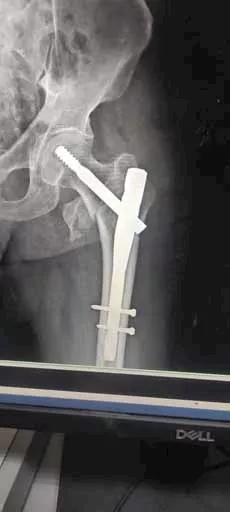

وفقًا لبيان المديرية، كشفت الفحوصات عن إصابة المُسن بكسر متفتت بأعلى عظمة الفخذ اليسرى، مما استدعى تدخلًا عاجلًا. وقام الفريق الطبي بتثبيت الكسر جراحيًا باستخدام مسمار نخاعي تشابكي.